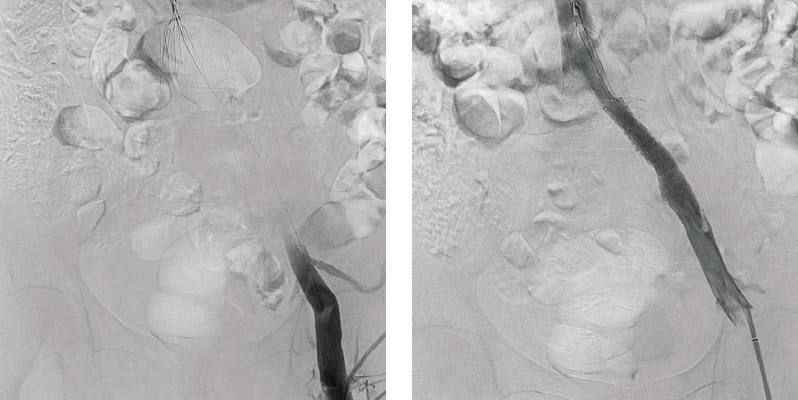

02急性下肢閉塞_before

別疾患で入院中だった患者様が急性下肢閉塞を起こしましたが、 速やかな治療で改善し、2 日後に退院しました。

02急性下肢閉塞_after